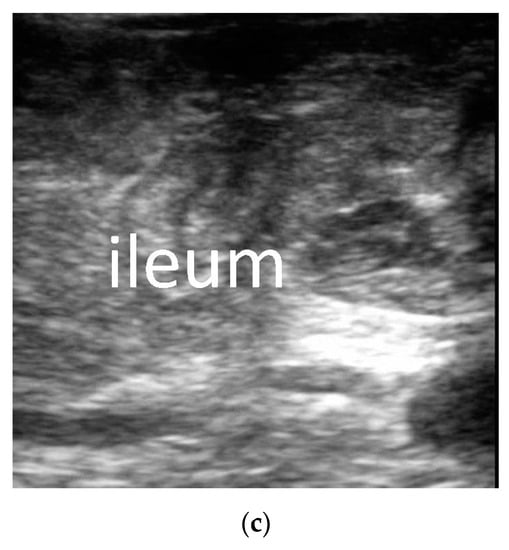

3.2.2. The Corresponding Ultrasound Findings of Diseases Leading to Neonatal Ileus